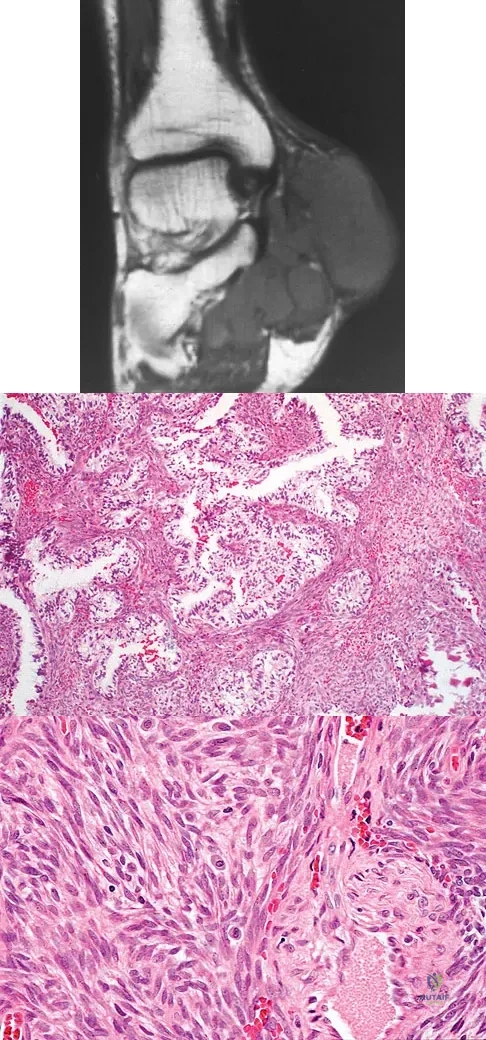

A 40-year-old man has a painless mass around his left ankle. He notes minimal growth over the past year. An MRI scan is shown in Figure 73a, and biopsy specimens are shown in Figures 73b and 73c. What is the most likely diagnosis?

Explanation

Figures 6a through 6d show the radiographs and biopsy specimens of an 8-year-old girl with leg pain. Management of the lesion should consist of

Explanation